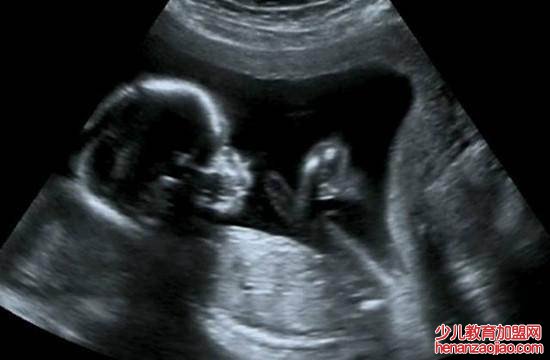

1、医学超声波检查:医学超声波检查的工作原理与声纳有一定的相似性,即将超声波发射到人体内,当它在体内遇到界面时会发生反射及折射,并且在人体组织中可能被吸收而衰减。因为人体各种组织的形态与结构是不相同的,因此其反射与折射以及吸收超声波的程度也就不同,医生们正是通过仪器所反映出的波型、曲线,或影象的特征来辨别它们。此外再结合解剖学知识、正常与病理的改变,便可诊断所检查的器官是否有病。